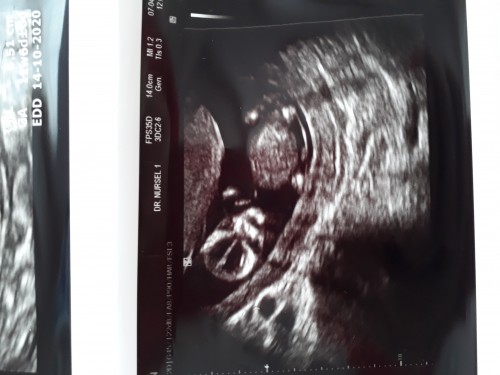

image

Bence kız......

Kesinlikle erkek :) öğrenince yaz bana :)

Bugün kesinleşti kesin erkek :))

Bence kiz direk gorur gornez dedim yani

Tatlı bır kız♥️☺️